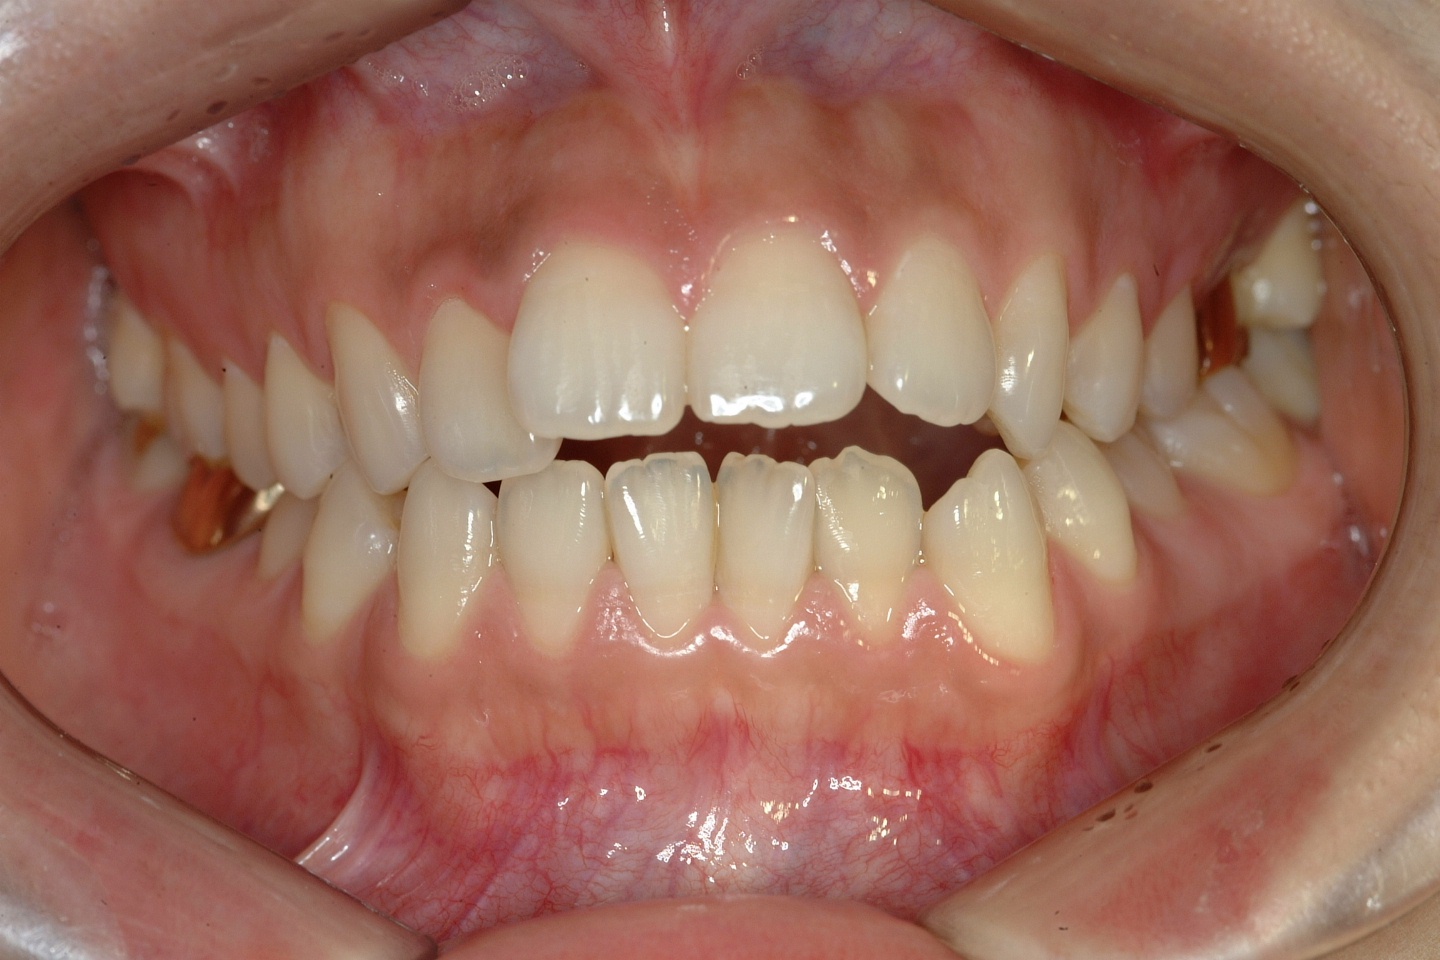

치료 전 사진입니다.